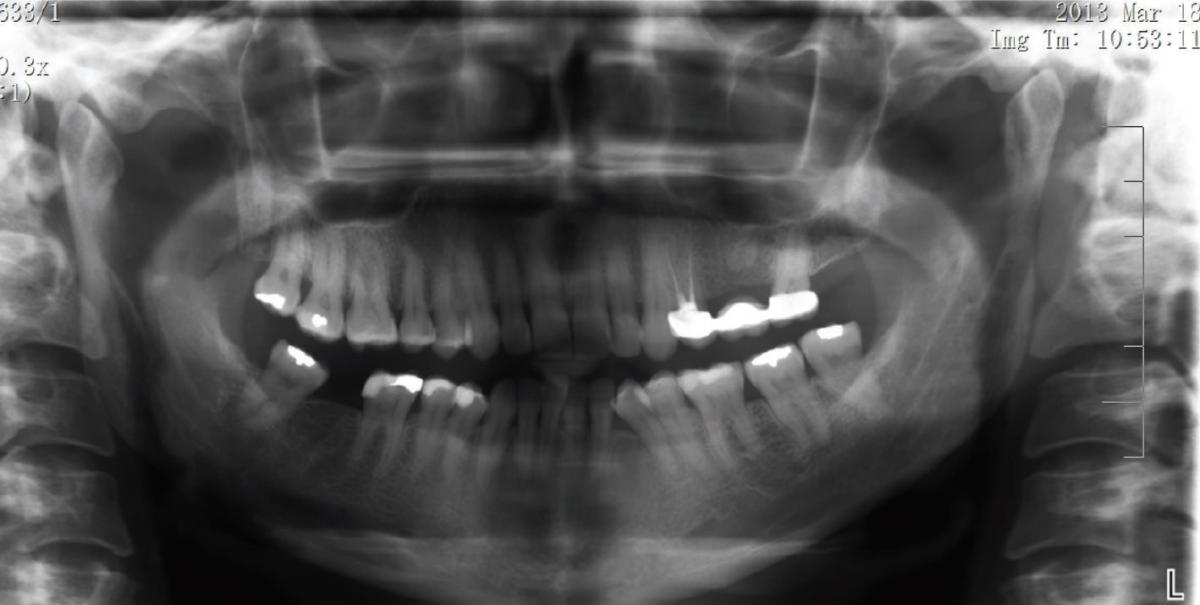

Примерно через 48 часов после инцидента при внеротовом обследовании был выявлен значительный отек мягких тканей, проходящий от левой подглазничной области к краю нижней челюсти. Также наблюдались кровоподтек в подглазничной области и незначительное посинение около носогубной складки (фото 1). При обследовании полости рта не было идентифицировано никаких признаков изъязвления слизистой, как и признаков некроза. Проблемный зуб, который подвергался лечению, был чувствителен к вертикальной и горизонтальной перкуссии. На ортопантомограмме были обнаружены признаки предыдущего эндодонтического лечения с просветлением в области верхушки корня (фото 2).

Фото 2: Ортопантомограмма, на которой были обнаружены признаки предыдущего эндодонтического лечения и просветление в области верхушки корня.